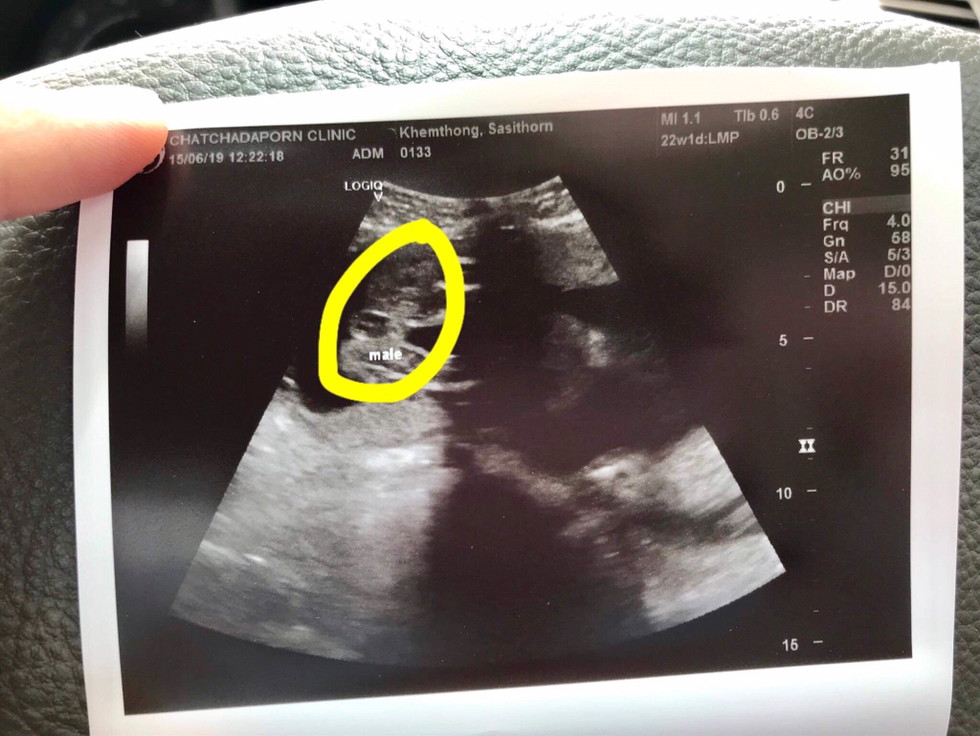

ผช ค่ะ

ผช.ค่ะ

ชายคะ